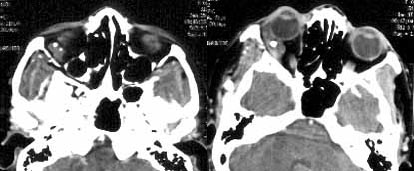

女性,35岁,右眼痛1周余,伴视物模糊,2年前有右眼出血史。

ct平扫,右眶内右下象限、外直肌外见团块状肿物,内散在结节状钙化。

增强扫描,肿物内可见明显强化的血管影。

ct诊断:右眶内海绵状血管瘤。